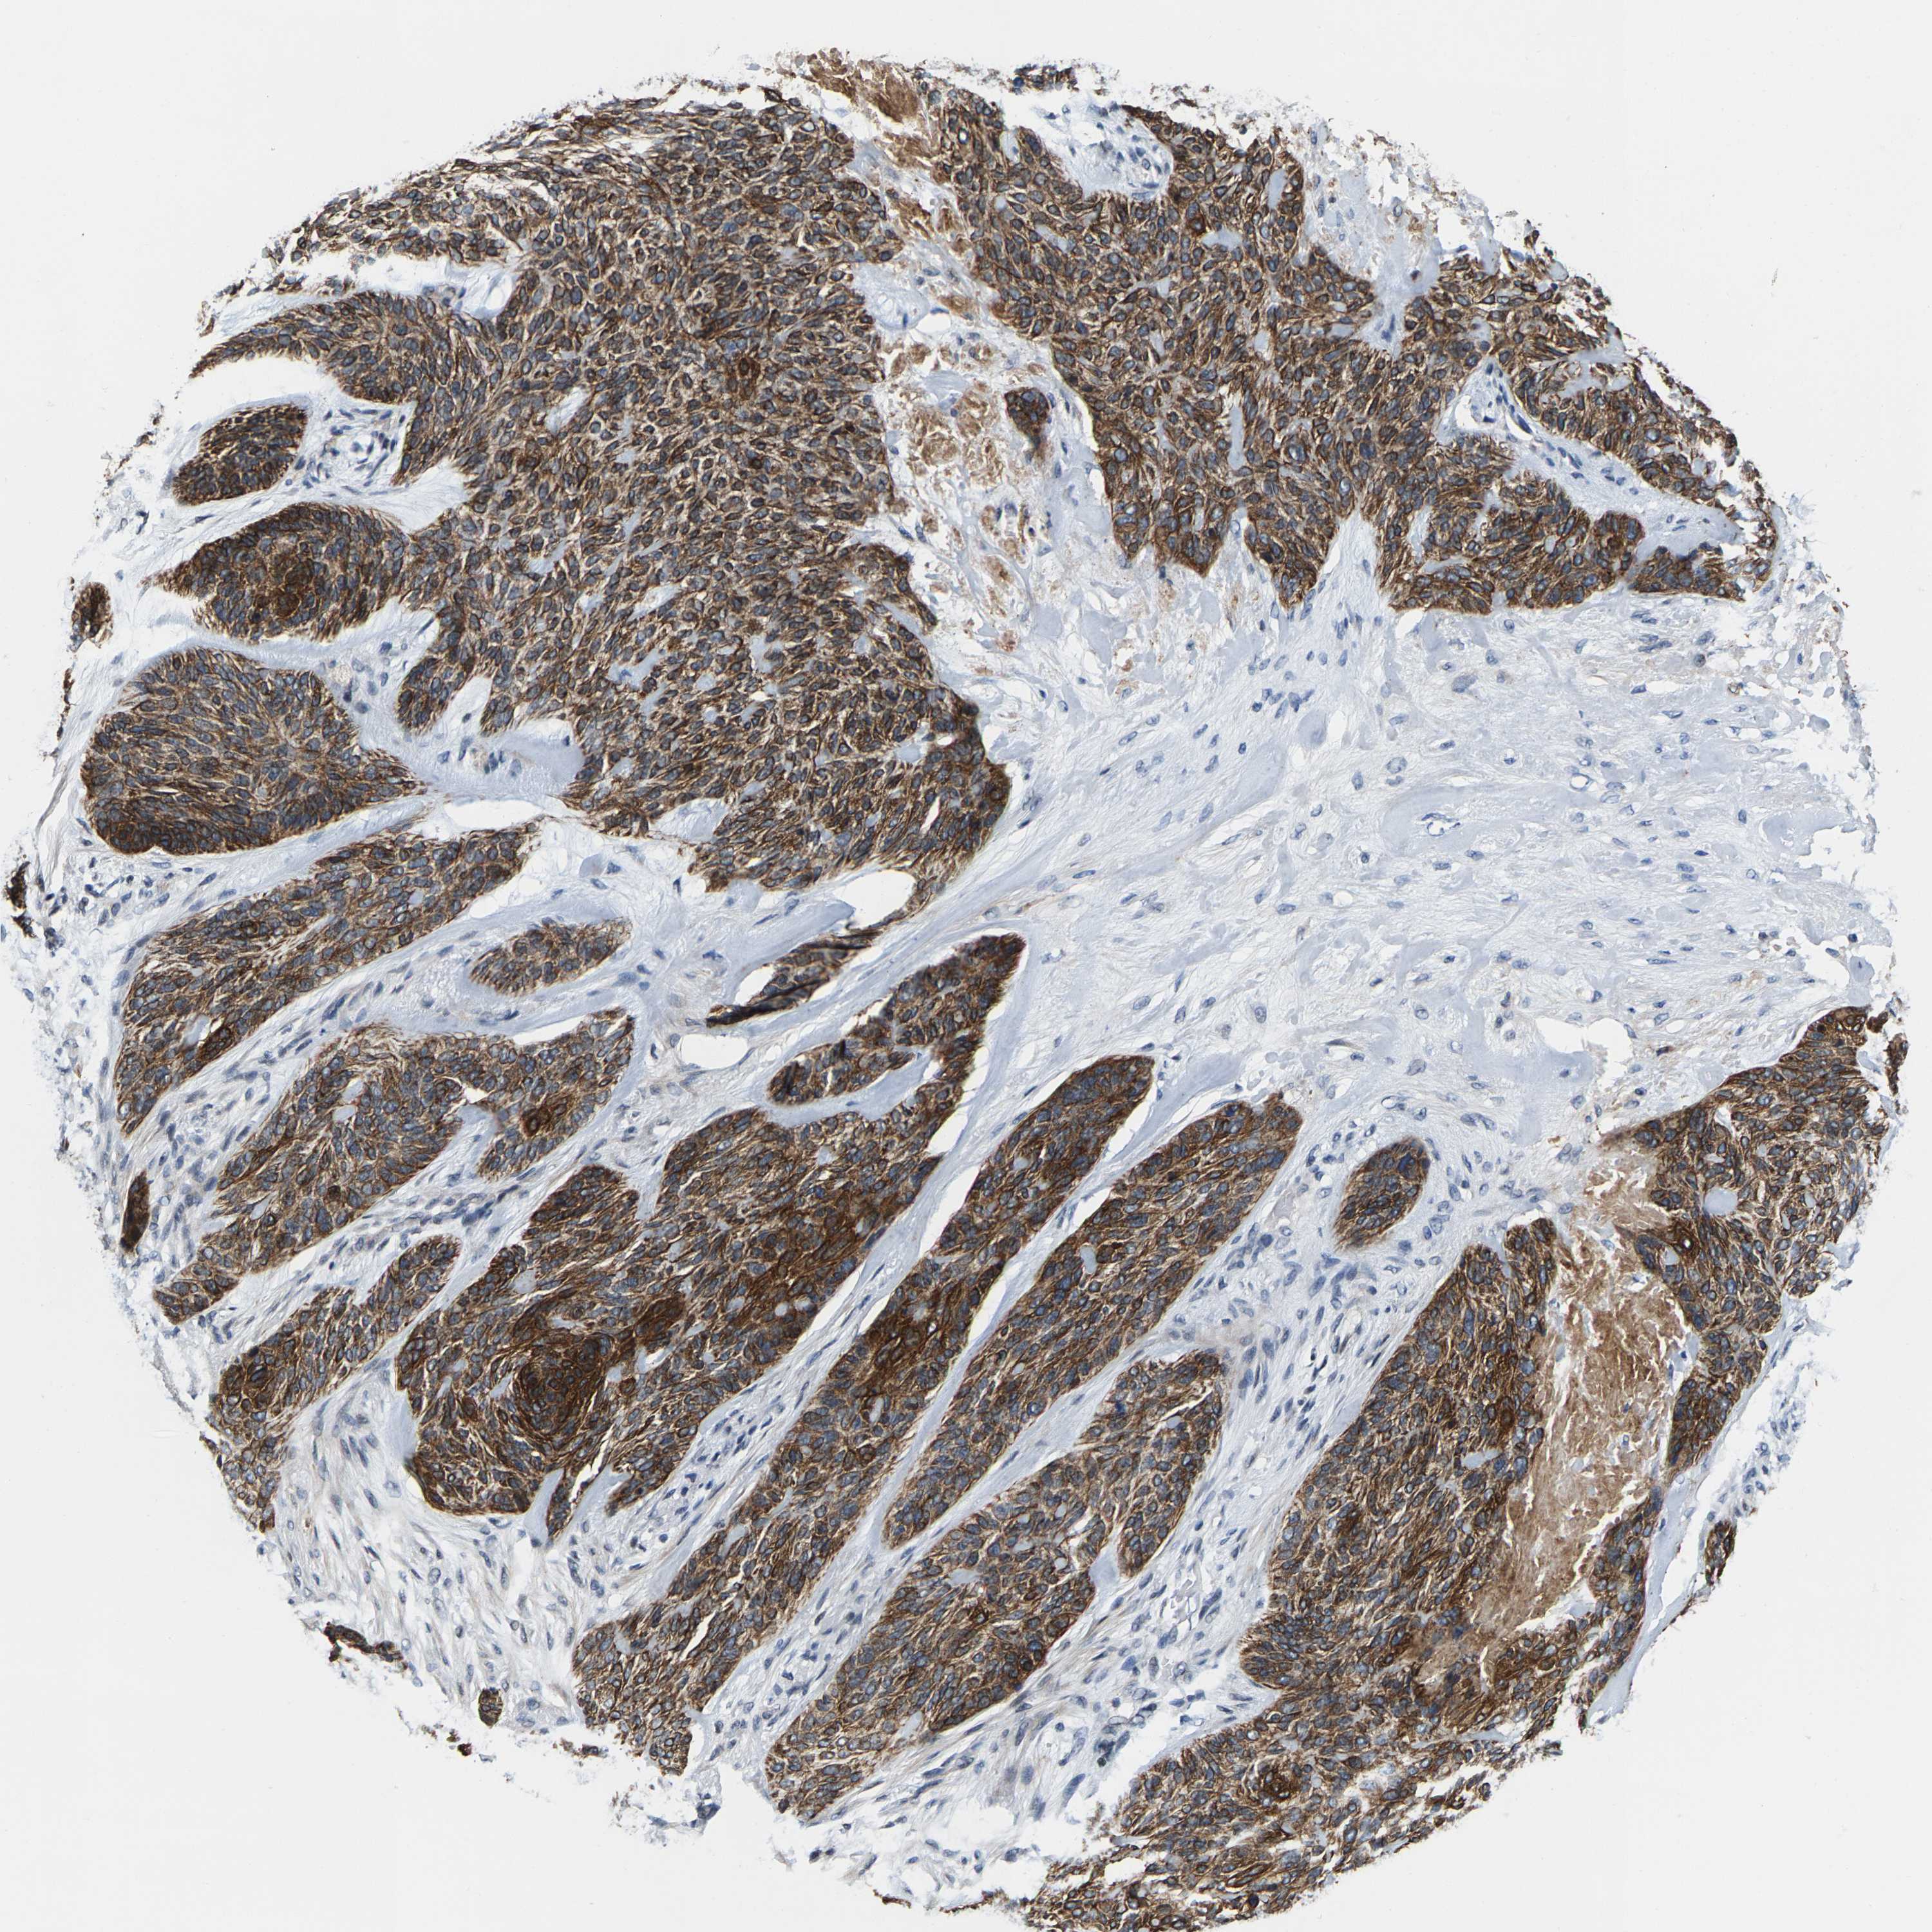

SKIN CANCER - Protein expressioni

A mouse-over function shows sample information and annotation data. Click on an image to view it in a full screen mode. Samples can be filtered based on level of antibody staining by selecting one or several of the following categories: high, medium, low and not detected. The assay and annotation is described here.

Antibody staining in the annotated cell types in the current human tissue is reported as not detected, low, medium, or high, based on conventional immunohistochemistry profiling in selected tissues. This score is based on the combination of the staining intensity and fraction of stained cells.

Each image is clickable and will lead to virtual microscopy that enables deeper exploration of all samples and also displays staining intensity scores, fraction scores and subcellular localization as well as patient and tissue information for each sample.

Antibody HPA021076

Staining

High

Intensity

Strong

Quantity

>75%

Location

Nuclear

Squamous cell carcinoma, NOS